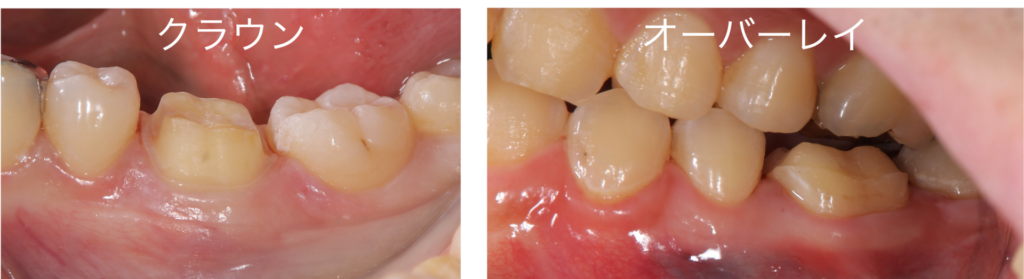

クラウンとオーバーレイの削る量の比較

このようにクラウンとオーバーレイの削る量を比較してみると、明らかにオーバーレイの削る量が少ないことがわかります

オーバーレイの削る量は、クラウンの削る量の50%とも言われています